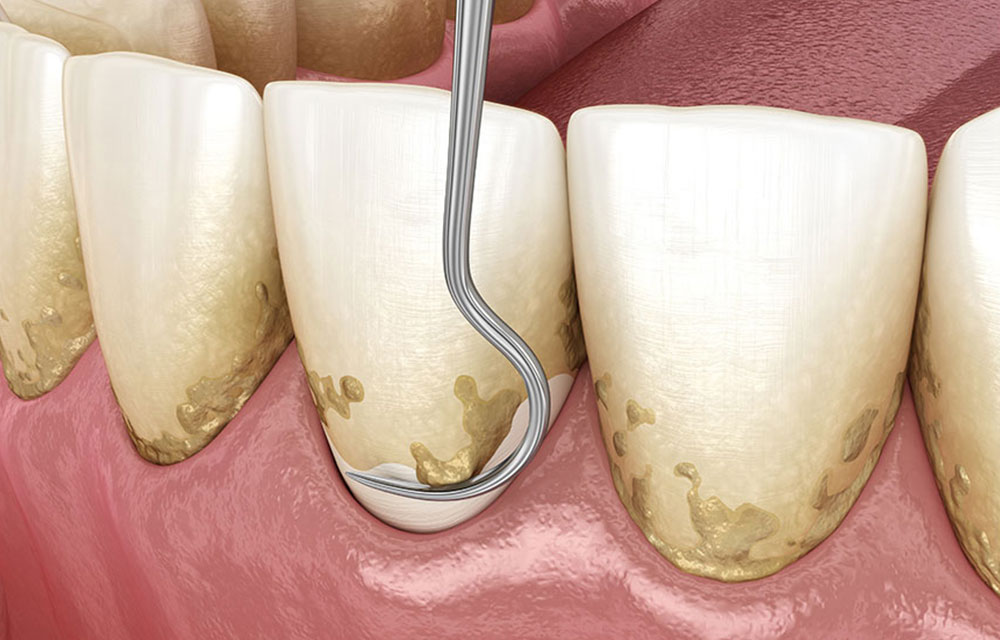

スケーリング・ルートプレーニング

ブラッシングだけで除去できないプラークや歯石は、歯医者で専用器具を使用して取り除きます。これをスケーリングと言います。また、歯石や細菌の毒素で汚染された物資を除去するルートプレーニングも同時に行います。